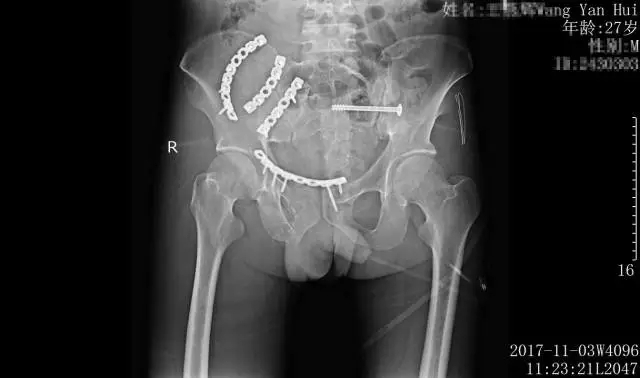

術后影像檢查,骨盆骨折端完全吻合

骨盆多發(fā)骨折考慮骨盆前、后環(huán)均為不穩(wěn)定,既有前后暴力損傷,也有垂直暴力損傷,手術指證明確。醫(yī)生經綜合考慮,決定以控制再次損傷為主,采用左側骶髂關節(jié)行閉合空心螺釘固定,右側髂骨翼及恥骨上支骨折行腹直肌外側入路行骨折固定,以一個小切口解決大半骨盆環(huán)的復位固定。

手術如期進行,在黃東永醫(yī)學團隊的共同努力下,骨盆骨折骶髂螺釘內固定及腹直肌外側入路處理復雜骨盆骨折手術順利完成,標志著惠州三院骨科醫(yī)學中心對復雜骨盆骨折微創(chuàng)手術又邁進了一大步。

術后,患者生命體征平穩(wěn),無副損傷出現。一期骨盆骨折手術后1周,患者再次進行了二期四肢骨折重建手術,術后病情穩(wěn)定,獲得了良好的治療效果,目前正在積極的康復當中。